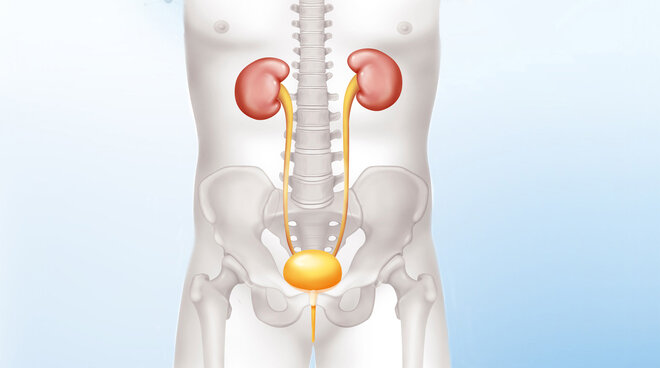

Aufbau und Funktion der Niere